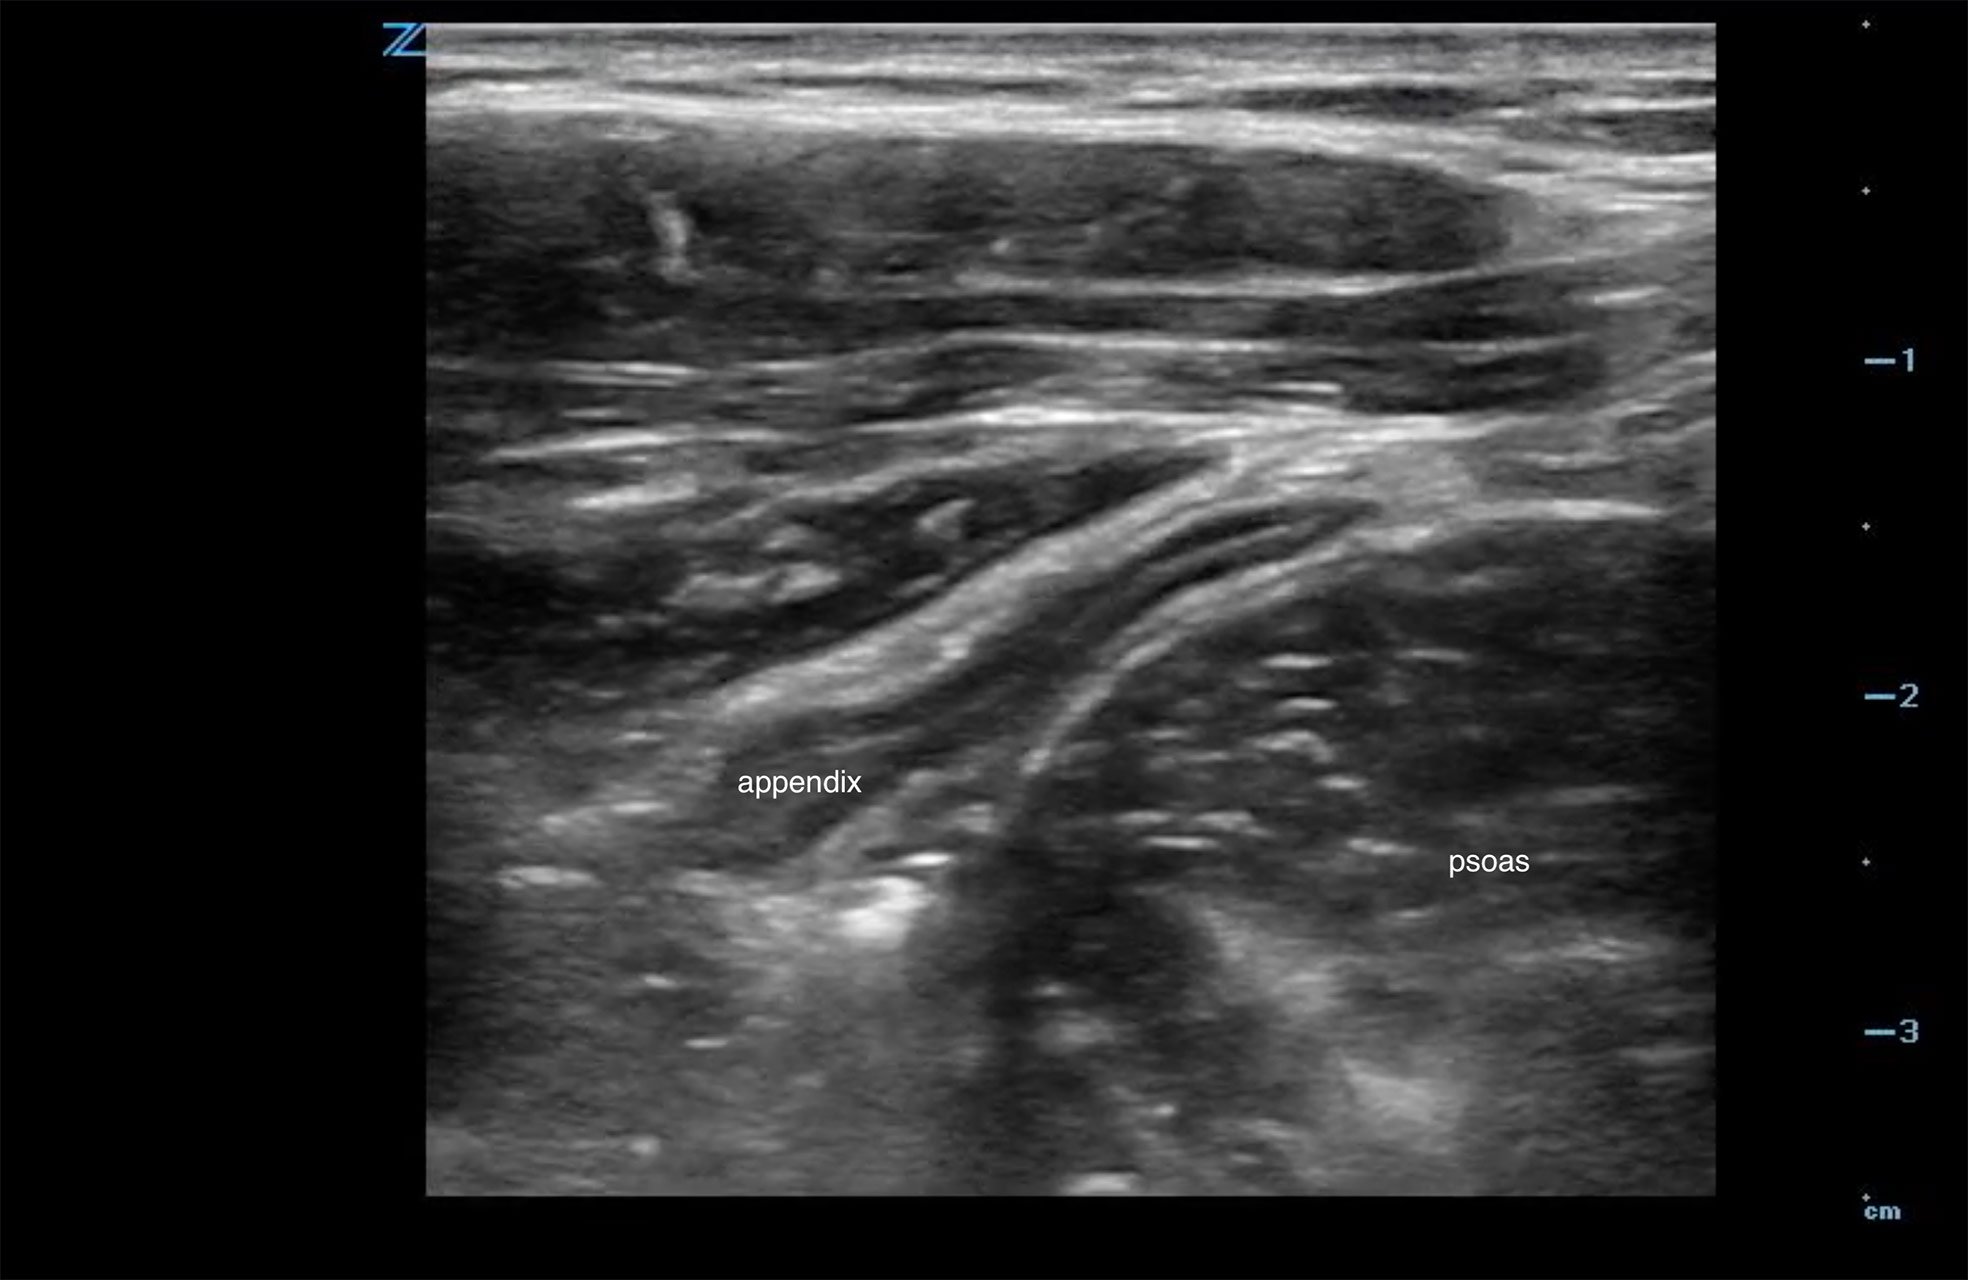

When scanning in the right lower quadrant, the two landmarks that are used to help identify the appendix are the psoas muscle and the iliac vessels (Figure 1).

Figure 1. Typical location of the appendix anterior to both the psoas and iliac vessels

- Localize the landmarks in the right lower quadrant. Identify the psoas muscle and the iliac vessels.

- Localize the appendix, which is typically anterior to the psoas and iliac vessels (Figure 1).

The following video shows a normal appendix lying just anterior to the psoas and iliac vessels

Video 2a, b. Position of appendix anterior to the psoas muscle and iliac vessels.